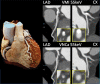

Novel photon-counting detector CT (PCD-CT) has the potential to address the limitations of previous CT systems, such as insufficient spatial resolution, limited accuracy in detecting small low-contrast structures, or missing routine availability of spectral information. In this review article, we explain the basic principles and potential clinical benefits of PCD-CT, with a focus on recent literature that has grown rapidly since the commercial introduction of a clinically approved PCD-CT.